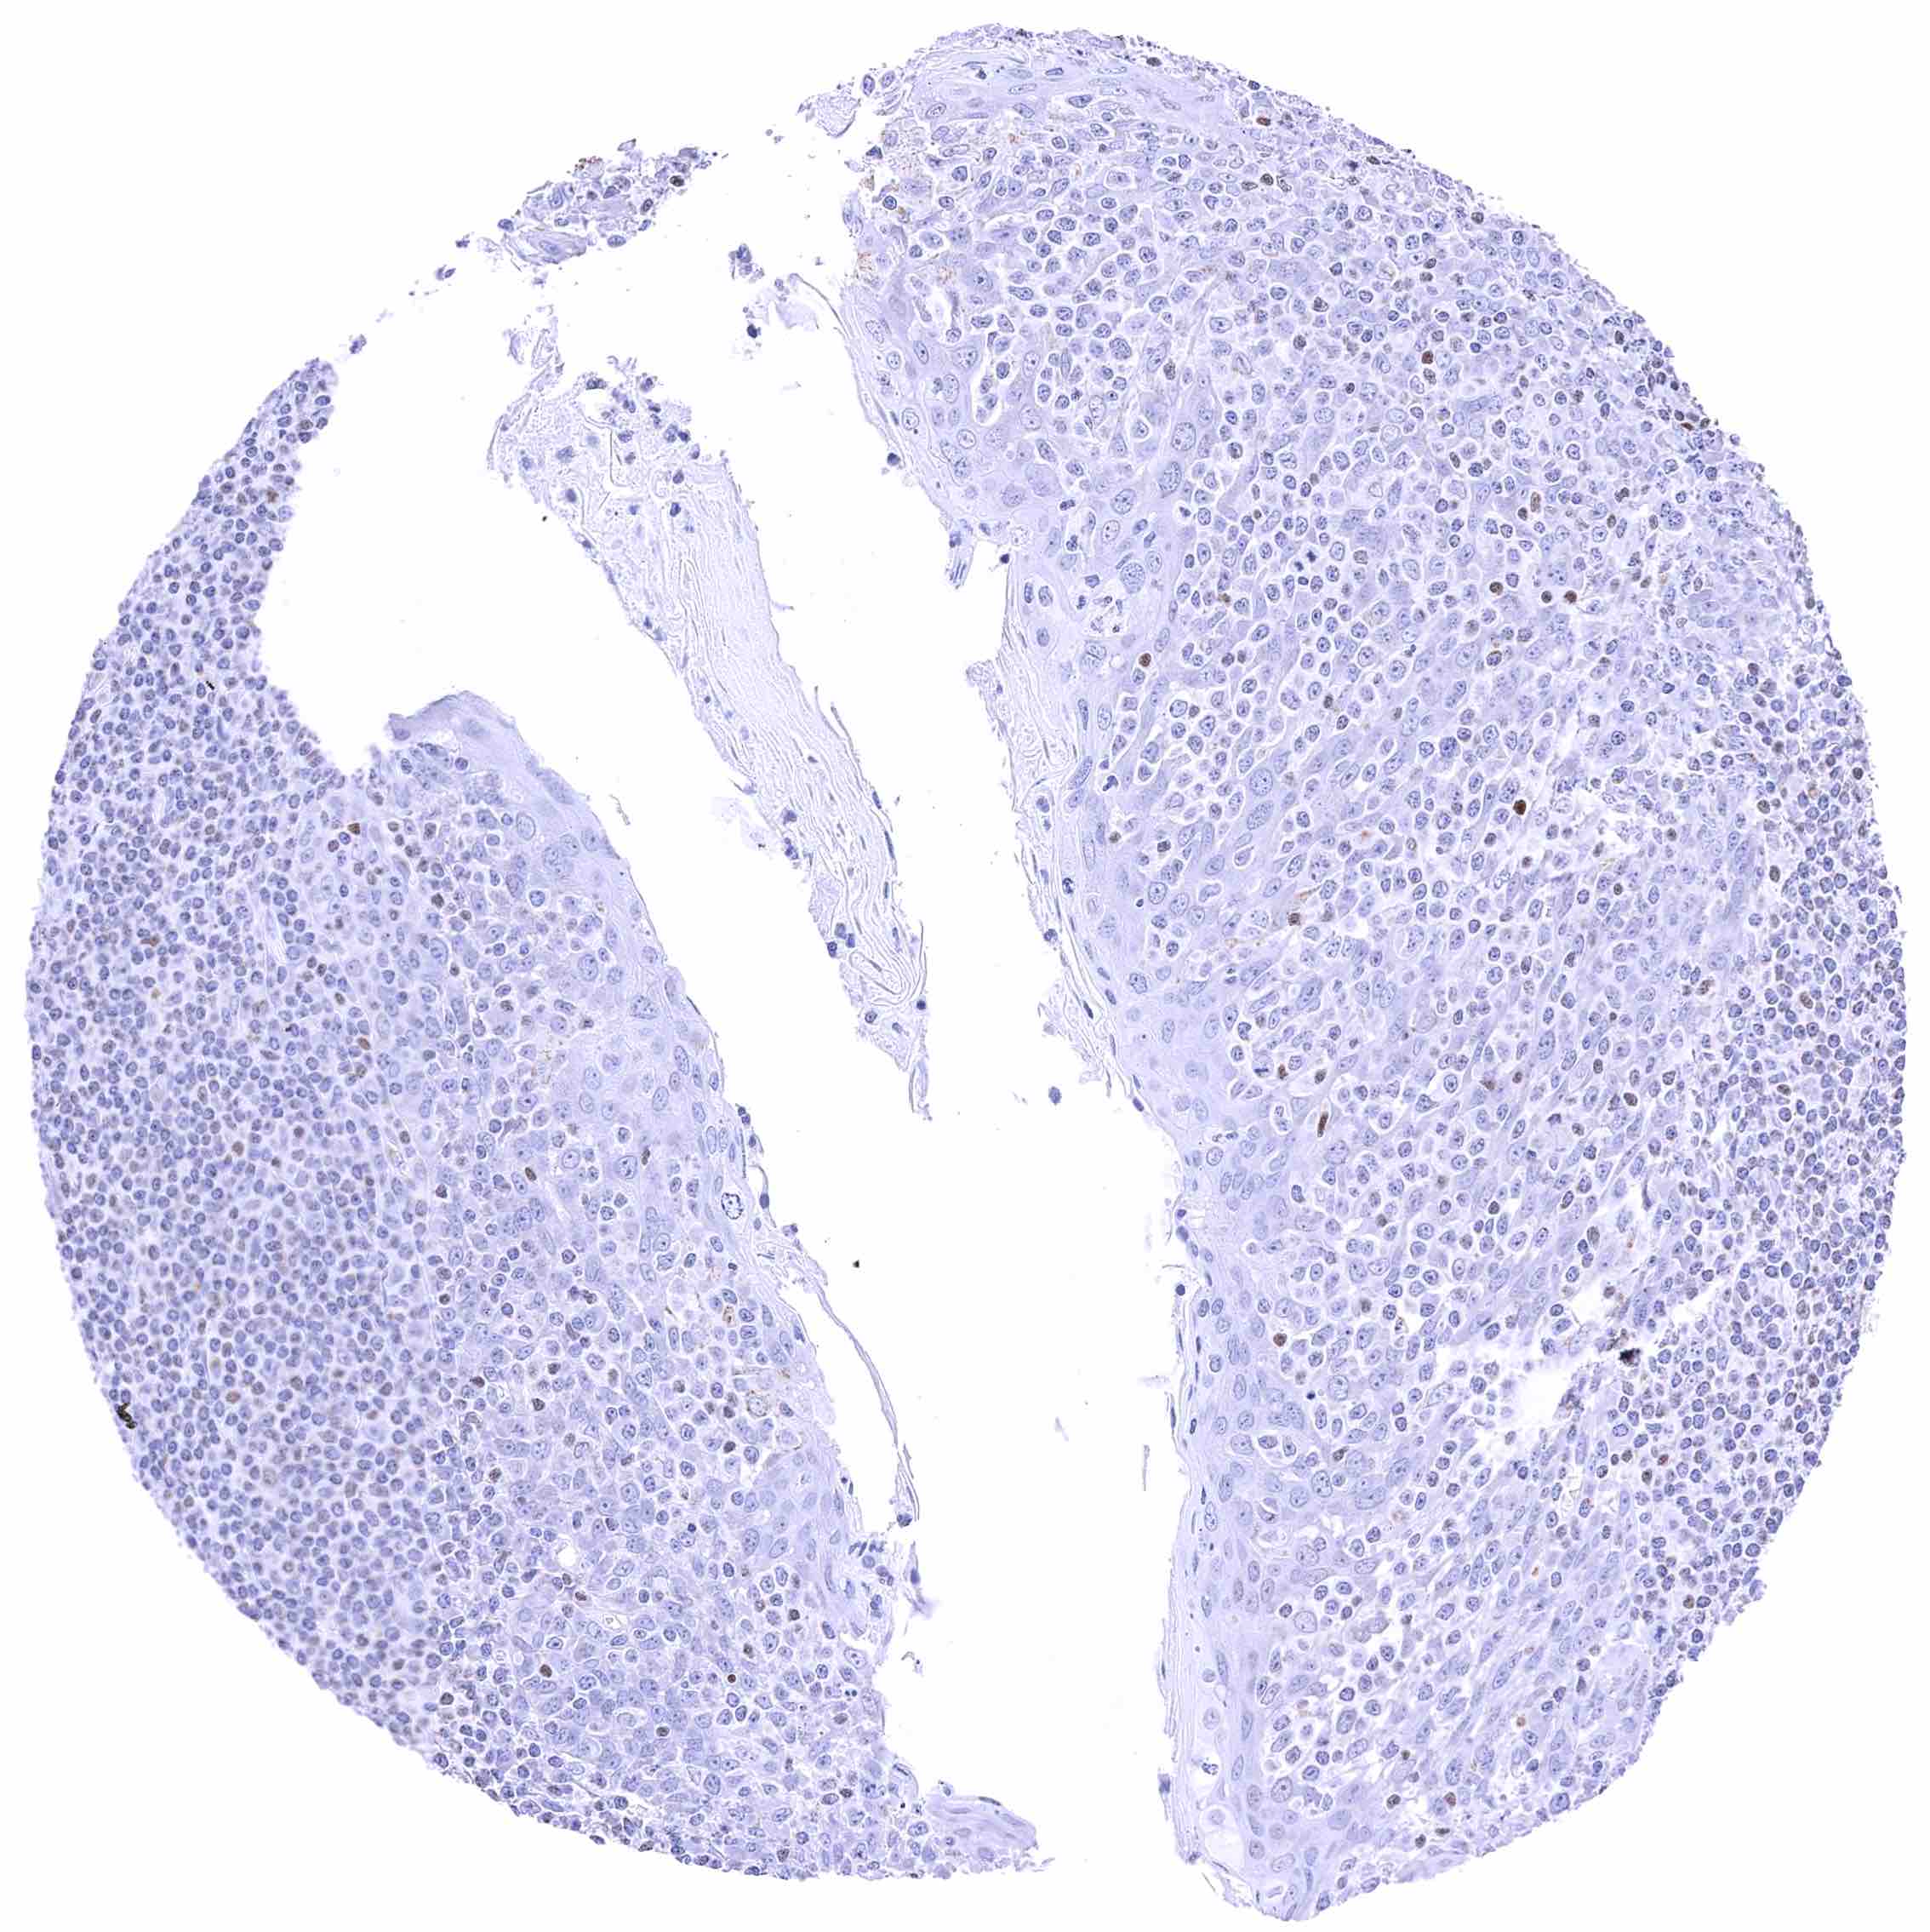

Thymus – Moderate to strong, nuclear GATA3 staining of a large fraction of lymphocytes. .jpeg